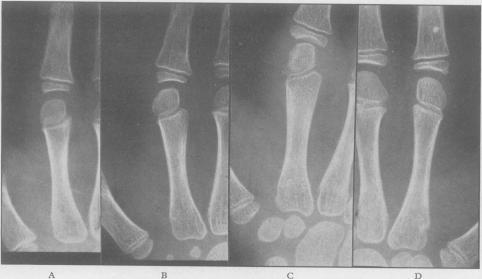

Juvenile rheumatoid arthritis (Still's disease).